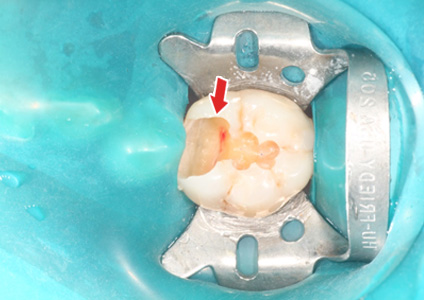

¡ã ÃæÄ¡Ä¡·á Áß¿¡ Ä¡¼ö°¡ ³ëÃâµÈ ¸ð½À